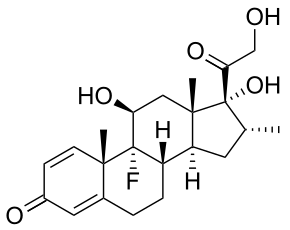

Anti-inflammatory drugs

Dexamethasone (DEX) is a glucocorticoid that is used as an anti-inflammatory and immunosuppressive agent. PLGA nanoparticles loaded with DEX via oil-in-water emulsion/solvent evaporation method can be embedded in alginate hydrogel matrices. To quantify the amount of DEX that was successfully seeding into the nanoparticle, UV spectrophotometry can be used. It has been shown that the amount of DEX that can be successfully loaded into the nanoparticles was ≈13 wt% and the typical particle size ranged from 400 to 600 nm.